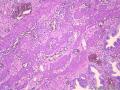

| 性别 | 女 | 年龄 | 44岁 | 临床诊断 | .胆总管下段结石并急性胆管炎 2.急性胆源性胰腺炎 3急性胆囊炎。 |

| 一般病史 | 上腹疼痛伴反复呕吐7天。血生化:ALT 268.0U/L,AST 157.0U/L,TBIL 64.3umol/L,DBIL 20.9umol/L,血糖:4.6mmol/L、血淀粉酶:3197.0u/L.腹部彩超示:胆总管上段结石并扩张。胰腺回声稍增粗声像。胆囊壁强回声实体物声像(考虑胆囊息肉)。 | ||||

| 标本名称 | 胆囊 | ||||

| 大体所见 | 灰绿、暗红色胆囊一枚,临床已局部剖开,大小:10x1-3.5x1.2cm。颈管开口直径0.4cm。囊内见胆汁,未见结石,近胆囊底部见长径0.1-0.4cm灰黄色息肉2枚,壁厚0.3-0.5cm,粘膜面粗糙似草莓状。 | ||||